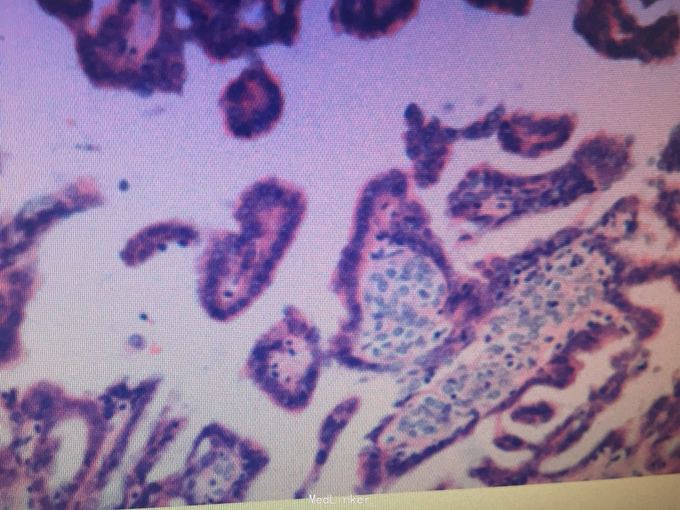

诊断 : 卵巢交界性囊腺瘤复发 治疗:探查见:盆腹腔无积液,腹膜光滑,胃、肝表面光滑,未及大网膜,常规表面光滑,子宫常大、表面光滑,左附件缺如,右卵巢来源囊实混合性肿物与子宫后壁、直肠、乙状结肠及盆底腹膜致密粘连,未见正常卵巢组织,右侧输卵管与周围粘连。行右附件切除术。术中冰冻回报乳头状囊腺瘤,部分交界性。尊重患者及家属选择,坚决要求保留子宫。